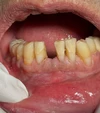

Diş Ağrısı

Diş Çürükleri

Diş Eksikliği

Diş ve Diş eti hastalıkları

Implant tedavisi